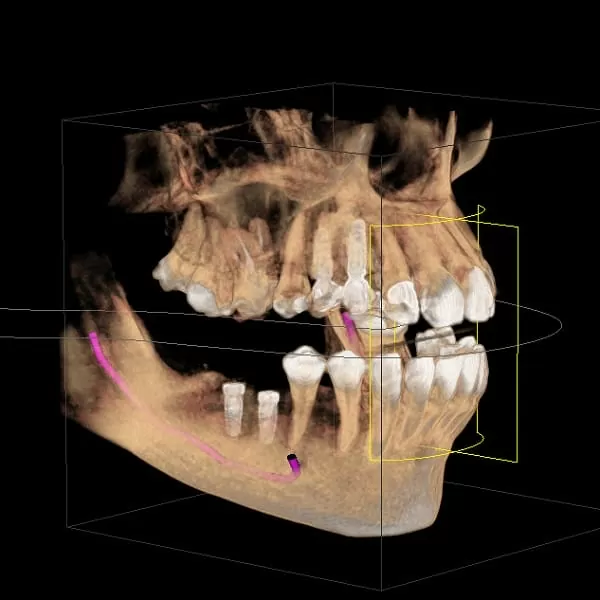

對於植牙醫師而言,CT的便利性,即是具有模擬植體植入的功能(圖2)。因為每位患者的顎骨結構不同,為了因應病人口腔現況及符合牙齒對應的咬合功能,植牙醫師需考量在術前判斷植體植入的位置是否恰當,由於CT所拍攝出來的影像是立體的,可以360度旋轉(圖3),可進一步判斷齒槽骨的骨質及植體植入的寬度與深度以避免植牙常見的問題案例:上排植體穿過鼻腔造成鼻竇破裂或是下排植體不小心碰到齒槽骨神經,可能造成半邊臉麻痺等問題發生(圖4)。所以進行拍攝「口腔電腦斷層CT」也是對患者進行植牙手術的安全與保障。

(圖3) 3D立體影像清楚呈現牙齒與口腔狀況

(圖4) 3D全口影像,可清楚呈現下顎神經管,紫線表示神經管

植牙前在「口腔狀況的判讀」是非常重要的,傳統平面全口X光片簡稱PANO,它們「只能顯現平面影像,無法展示口腔狀況的切面與橫斷面,容易造成骨質與骨量判讀上的誤差。CT則是呈現3D影像,並且有一個專屬的視窗(圖5),可以很清楚地往舌側的方向橫切過去,讓橫切面全部顯現出來。當醫師在與病人解說時,可以移動視窗顯示病人骨質的寬度及神經管的位置,另外可置入虛擬植體圖示(圖6),讓病人更清楚明白醫師的解說以及要為他植牙的位置及角度。

(圖5) CT呈現3D影像,醫師講解時可移動視窗顯示病人骨質的寬度及神經管的位置

(圖6) 置入虛擬植體,模擬適當的植牙位置